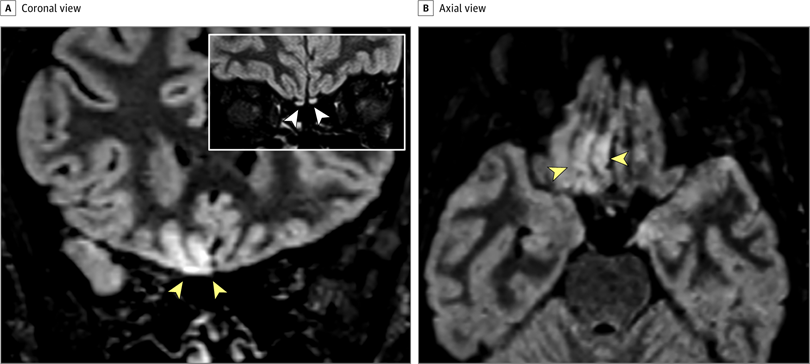

На 3-мерных и 2-мерных изображениях восстановления инверсии, ослабленных жидкостью, гиперинтенсивность коры была очевидна в правой извилине прямой мышцы ( Рисунок 1 ), а небольшая гиперинтенсивность присутствовала в обонятельных луковицах ( Рисунок 1 ). Потому что многие пациенты в Италии страдают аносмией.3, и изменение коркового сигнала свидетельствовало о вирусной инфекции, был проведен мазок, и анализ полимеразной цепной реакции с обратной транскрипцией дал положительные результаты для SARS-CoV-2. Во время контрольной МРТ, проведенной через 28 дней, изменение сигнала в коре полностью исчезло, а обонятельные луковицы стали тоньше и немного менее гиперинтенсивными ( рис. 2, 4 ). Пациент восстановился от аносмии. У 2 других пациентов с COVID-19 с аносмией, которым проводилась МРТ головного мозга через 12 и 25 дней с момента появления симптомов, аномалий головного мозга не наблюдалось.

Рис. 1. Изменения изображений магнитно-резонансной томографии головного мозга у пациента с коронавирусной болезнью 2019 (COVID-19) с аносмией через 4 дня от начала симптома

Насколько нам известно, это первый отчет об участии мозга человека in vivo у пациента с COVID-19, показывающий изменение сигнала, совместимое с вирусной инвазией в мозг в кортикальной области (например, заднюю извилину прямой мышцы), которая связана с обонянием. Альтернативные диагнозы (например, эпилептический статус, изменения, подобные синдрому задней обратимой энцефалопатии, другие вирусные инфекции и анти- N- метил- d-аспартатный рецепторный энцефалит) маловероятны с учетом клинического контекста. Основываясь на результатах МРТ, включая незначительные изменения обонятельной луковицы, мы можем предположить, что SARS-CoV-2 может проникнуть в мозг через обонятельный путь и вызвать обонятельную дисфункцию нейросенсорного происхождения;

Для подтверждения этой гипотезы необходимы исследования спинномозговой жидкости и патологии. Наши и другие наблюдения за нормальной визуализацией головного мозга у других пациентов с обонятельной дисфункцией, связанной с COVID-19 4и исчезновение аномалий кортикальной МРТ при последующем исследовании этого пациента позволяют предположить, что изменения визуализации не всегда присутствуют при COVID-19 или могут быть ограничены очень ранней фазой инфекции. Кроме того, аносмия может быть преобладающим проявлением COVID-19, и это следует учитывать при выявлении и изоляции пациентов с инфекцией, чтобы избежать распространения болезни.